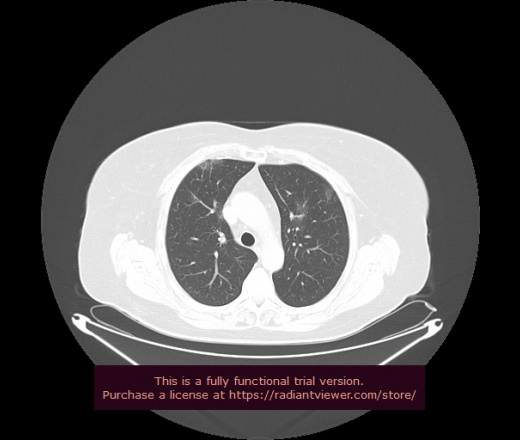

Уважаемые коллеги, если имеется интерес, сможете ли Вы спрогнозировать дальнейшее +-одинаковое течение процесса у 4 данных разных пациентов? Зацепиться где-то можно очень просто, где-то нельзя.